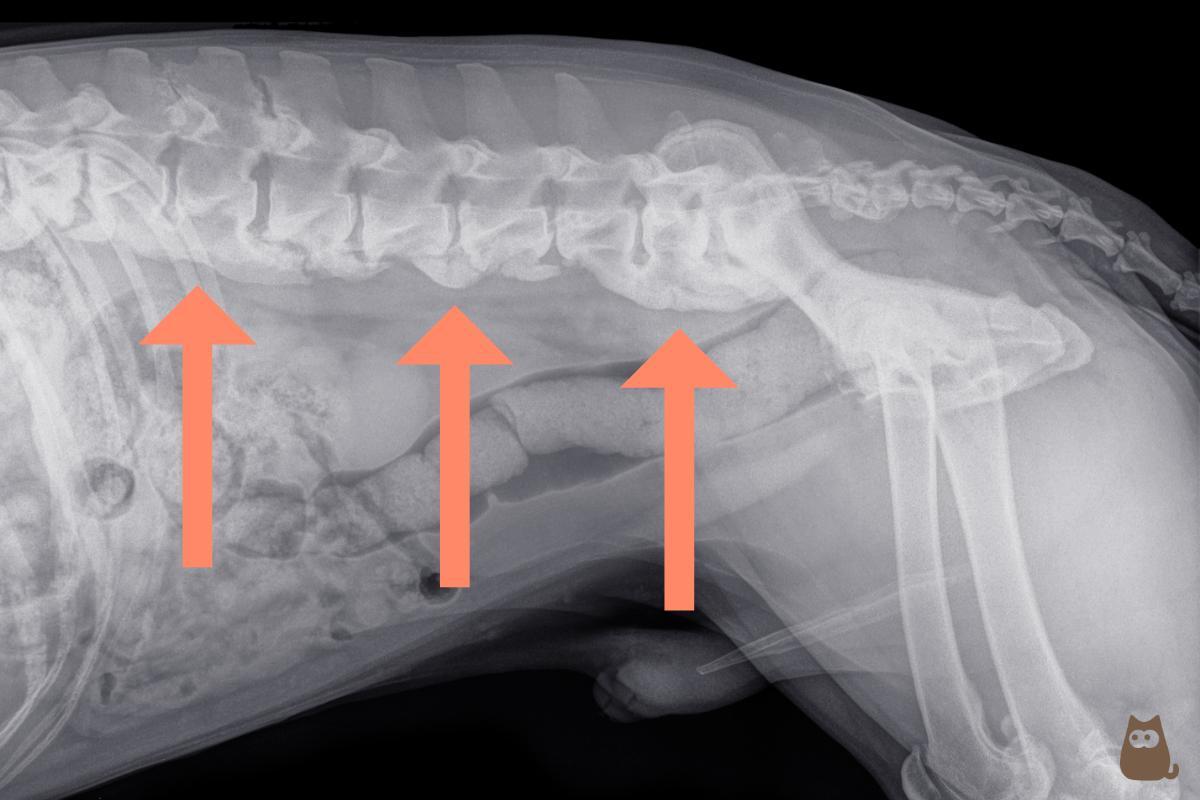

O diagnóstico de espondilose deformante canina é simples e é realizado por meio de radiografia. No entanto, é importante incluir um exame neurológico completo dentro do protocolo para poder detectar possíveis danos neurológicos produzidos pela espondilose.

No exame radiográfico, a espondilose é observada em forma de protusões (osteófitos) da borda inferior das vértebras até os extremos anterior e posterior das vértebras adjacentes. À medida que avança, adquire um aspecto em forma de gancho que comumente recebe o nome de "bico de papagaio". Nos casos mais avançados, chega a se formar uma ponte que une dois corpos vertebrais em nível ventral. Quando somente se observa um osteófito na vértebra, se pode chamar de espondiloartrose canina.

Diante deste tipo de lesão, é importante realizar um diagnóstico diferencial com outros processos que também ocorrem com a formação de osso novo, como os tumores vertebrais ou a espondilite. No entanto, um simples exame radiológico permitirá distinguir a espondilose destas outras patologias.